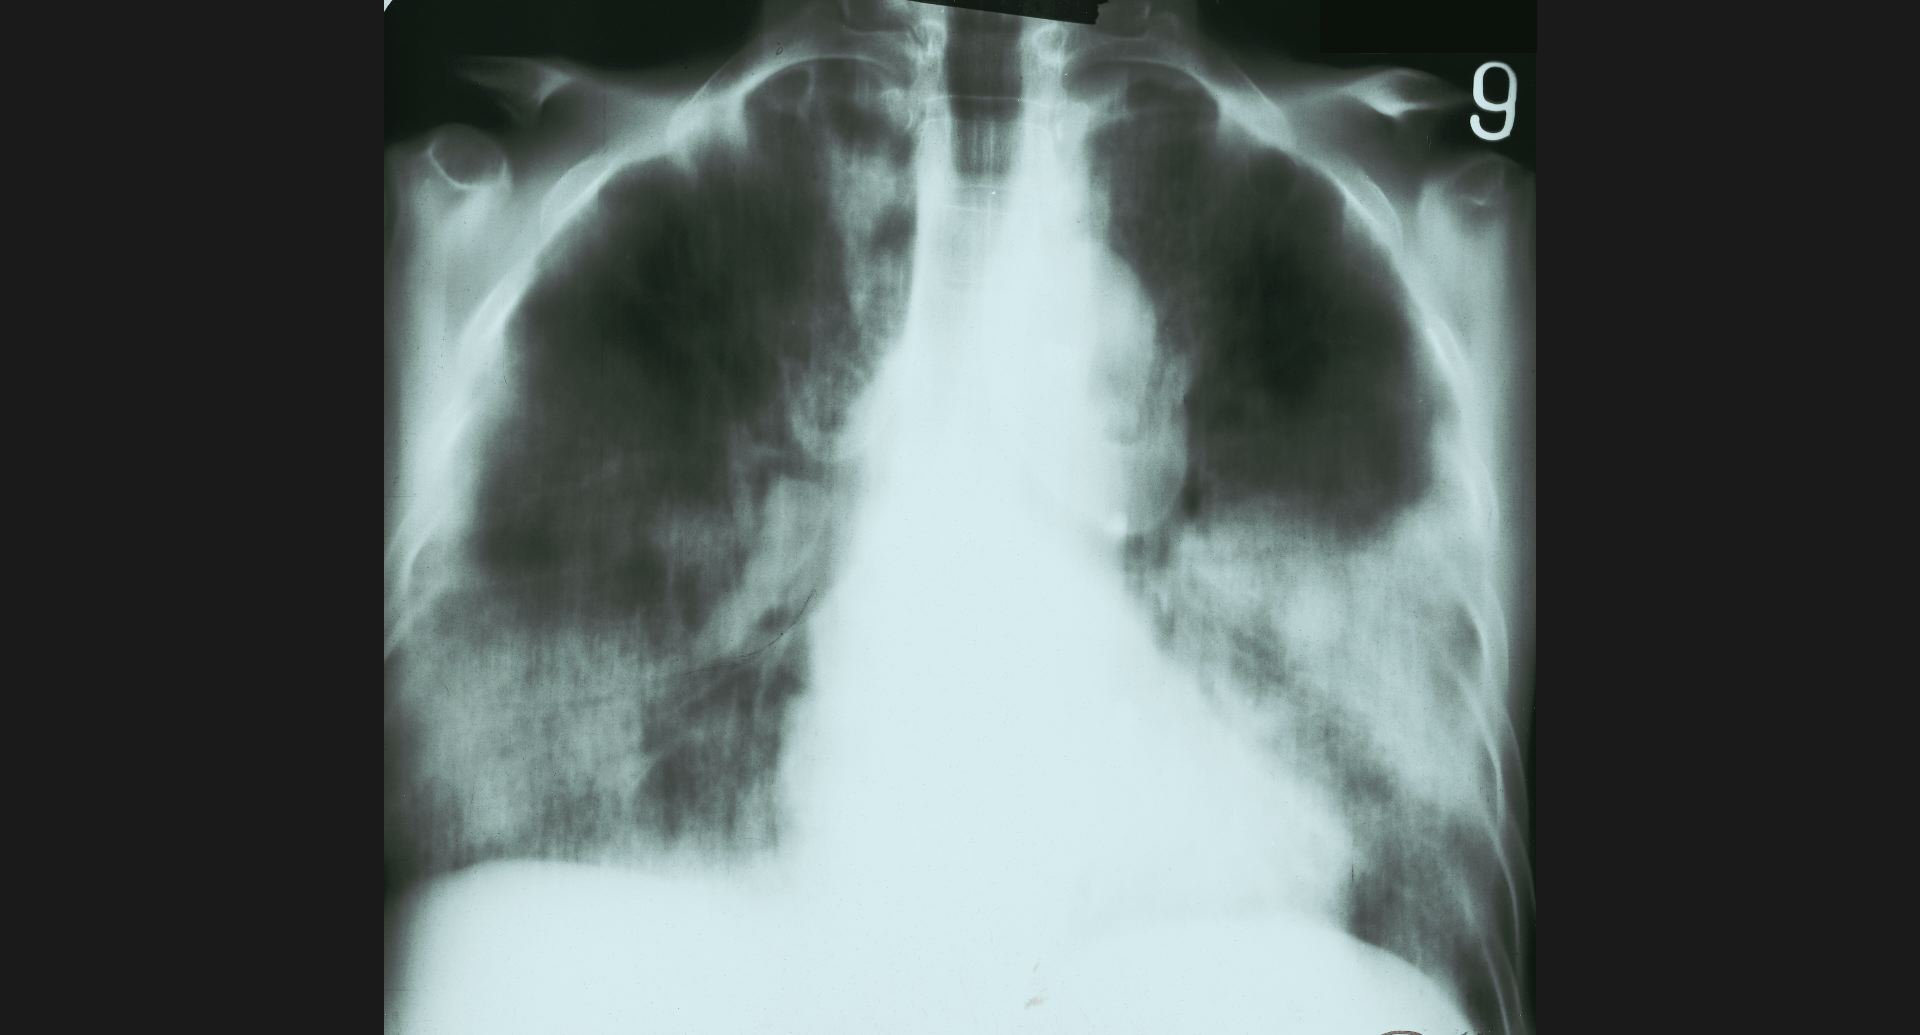

fig.8(87KB)

:Lung abcesscavity。